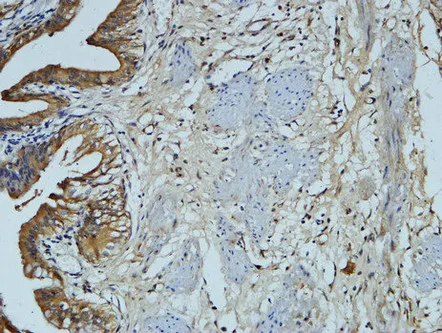

HER2(11H9)Mouse Monoclonal Antibody

Cat: AMM11986

Size1:50μL Price1:$118

Size2:100μL Price2:$220

Size3:200μL Price3:$380

Application:WB,IF-P,IF-F,ICC/IF,IHC-P

Reactivity:Human,Mouse,Rat

Conjugate:Unconjugated

Optional conjugates: Biotin, FITC (free of charge). See other 26 conjugates.

Gene Name:ERBB2